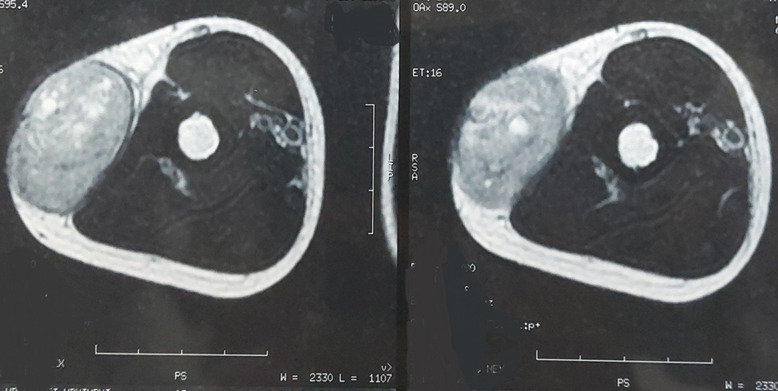

Ewing家族软组织肿瘤(EFT)代表了一种不确定组织发生的肿瘤谱,发生在没有骨累及的软组织中。它们包括骨骼外尤文氏肉瘤和原始神经外胚层肿瘤。这些肿瘤在形态上与骨骼系统的尤文氏肉瘤难以区分。已知易位相关肿瘤,它们具有共同的非随机易位,导致EWSR1基因在22q12区域与ETS家族转录因子中的一个成员融合。EFT主要发生在青少年和30岁以下的年轻男性中,几乎可以出现在任何地方,但最常见于四肢的深层软组织。本研究报告一例罕见的发生在14岁男孩上臂的EFT病例,他表现为右臂肿块疼痛发展了6个月,同时强调了这种罕见疾病的主要组织学,免疫组织化学和分子特征,以及相关诊断方法的原始流程图,用于鉴别诊断。

The Ewing family tumors (EFT) of soft tissue represent a spectrum of neoplasms of uncertain histogenesis, arising in soft tissue without bone involvement. They include Extraskeletal Ewing Sarcoma and Primitive Neuroectodermal Tumor. These tumors are morphologically indistinguishable from Ewing sarcoma of the skeletal system. Known to be translocation-associated neoplasms, they share a common non-random translocation leading to the fusion of the EWSR1 gene on the 22q12 region, with one of the many members of the ETS family of transcription factors. Occurring mainly in adolescents and young men under the age of 30, EFT´s may arise virtually anywhere, but are most common in deep soft tissues of the extremities. The purpose of this work is to report a rare case of an EFT arising in the upper arm of a 14-year-old boy, who presented with a painful right arm mass evolving for 6 months, while highlighting the main histological, immunohistochemical and molecular features of this rare condition, along with an original flow chart of a relevant diagnostic approach for differential diagnosis.